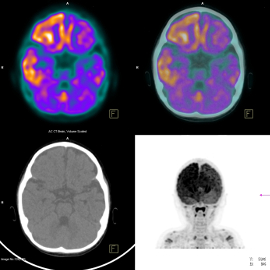

This four-year study involving 126 patients from across Europe compared two functional imaging techniques, PET and functional MRI (fMRI), with a well-established test, the Coma Recovery Scale-Revised (CRS-R)

This four-year study involving 126 patients from across Europe compared two functional imaging techniques, PET and functional MRI (fMRI), with a well-established test, the Coma Recovery Scale-Revised (CRS-R). It demonstrated that repeated testing with CRS-R and a PET scan using a specific imaging agent was about 74% accurate in predicting the extent of recovery within a year, compared with 56% for fMRI.

During the study, the PET scanning technique showed brain activity consistent with some level of consciousness in a third of the 36 patients who were diagnosed as unresponsive on the CRS-R test. This led the authors to conclude that CRS-R alone is not a reliable way of assessing consciousness, and supplementing it with this PET scan can lead to much more accurate results.